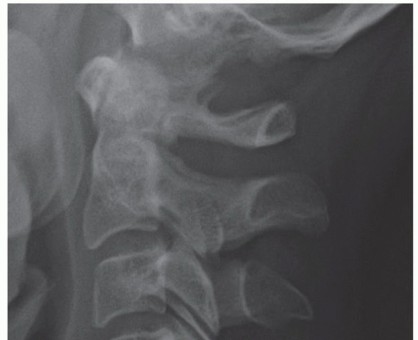

### FIG 3 • Hybrid constructs. This patient had retrovertebral cord compression behind C5 and disc-based compression at C6-C7. Rather than doing a two-level corpectomy of both C5 and C6, a corpectomy-discectomy construct allows for a shorter strut graft and intermediate points of screw fixation into C6. Exacerbation of axial neck pain can occur after laminoplasty in those who have significant complaints preoperatively, although it rarely becomes of significance in those who have little to no axial pain preoperatively. Also, adequate decompression may not occur after laminoplasty in those with kyphosis, as cord driftback away from anterior compressive lesions is unreliable in this setting. ##